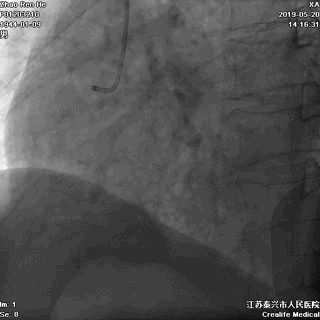

右冠几乎齐根闭塞

右向左无侧枝循环

RCA几乎齐根闭塞,非锥形残端

闭塞入口处有分支发出

闭塞出口处发出分支血管

CTO闭塞段长度小于20mm